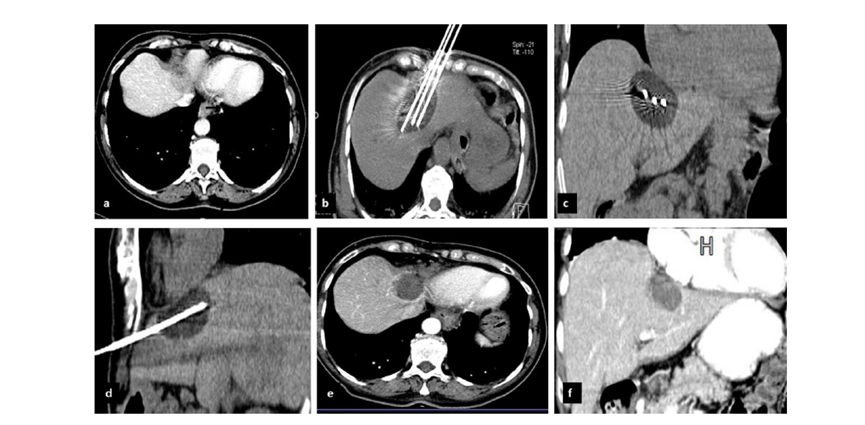

CT引导的冷冻消融

完全消融率为97%(66/68);2名患者均接受了额外的冷冻消融,随后实现完全消融。平均随访期为 12.8 个月(范围:3-27 个月)。所有患者均接受影像复查(CT 或 MRI)。11个病灶(16.2%)检测到局部肿瘤进展,6、12和18个月时的累积局部肿瘤进展率分别为4%、8.2%和20.5%。8例出现远处肝内或肝外病变的患者接受经动脉化疗栓塞、经动脉化疗栓塞加射频消融治疗或全身化疗。

主要和次要并发症发生率分别为3.5%(2/57)和22.8%(13/57)。并发症主要表现为局部皮肤冻伤、中度气胸、发热,仅有少数患者接受治疗,多数患者自行恢复。所有患者能耐受围手术期疼痛,VAS 评分范围在 1-3 分之间(平均 1.65分)。3例患者术后疼痛加重,VAS评分达到4~5分,患者口服止痛药后逐渐缓解。所有患者术后1天血常规、白细胞计数均升高,血小板均有不同程度下降,但变化值均在正常范围内。肝功能1个月后逐渐恢复到正常水平。